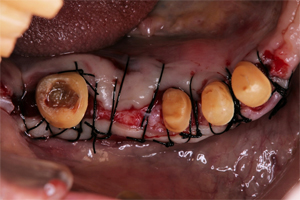

残存した歯を利用して可能な限り固定式のブリッジで対応できるよう歯周組織の再生を図りました。(再生療法)

抜歯した部位に

再生療法を実施

縫合

抜歯と歯周外科処置

上顎前歯部は保存不可能な歯の抜歯と歯周外科処置を行うことでブリッジが長持ちできるように歯周環境を整えました。

残存した歯を利用して可能な限り固定式のブリッジで対応できるよう歯周組織の再生を図りました。(再生療法)

術後、さらにブラッシングしやすいように歯周外科処置により歯肉を強化しました。